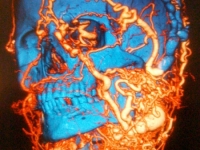

A multidisciplinary team of Vall d'Hebron University Hospital, in Barcelona, led by Dr. Joan-Pere Barret, head of Plastic Surgery and Burns, made a successful face transplant to reconstruct two thirds of a lower face, neck, mouth, tongue and pharynx.

The patient has been affected by a massive arteriovenous malformation for 20 years. The disease has caused a progressive deformation of the tissues. The patient, due to the evolution of his illness, had important functional alterations, such a vision problems, speech and risk of severe bleeding that put his life at risk. This is the first time that a transplant of this complexity is performed in the world.

The patient had been examined in several international hospitals (Mayo Clinic, Harvard, etc.) where he was considered inoperable. The evolution of the disease, a progressive deformity and severe bleeding that had put his life at risk, was assessed by the face transplant team of Vall d'Hebron, which considered that the only treatment option for this patient was removing his tumour tissues and rebuilding his face through a face transplant.

The operation, carried out in early February, was highly complex and lasted 27 hours. The team comprised 45 professionals from different departments of the Hospital: Plastic Surgery, Anaesthesia, Nursing, Nursing Assistants, Liver Transplant, Transplant Coordinator, Infectious Diseases, Interventional Neuroradiology, Intensive Care Unit, orderlies and all central and support services.